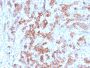

Positive Control

IHC, FFPE (verified)

IHC (FFPE) (verified)